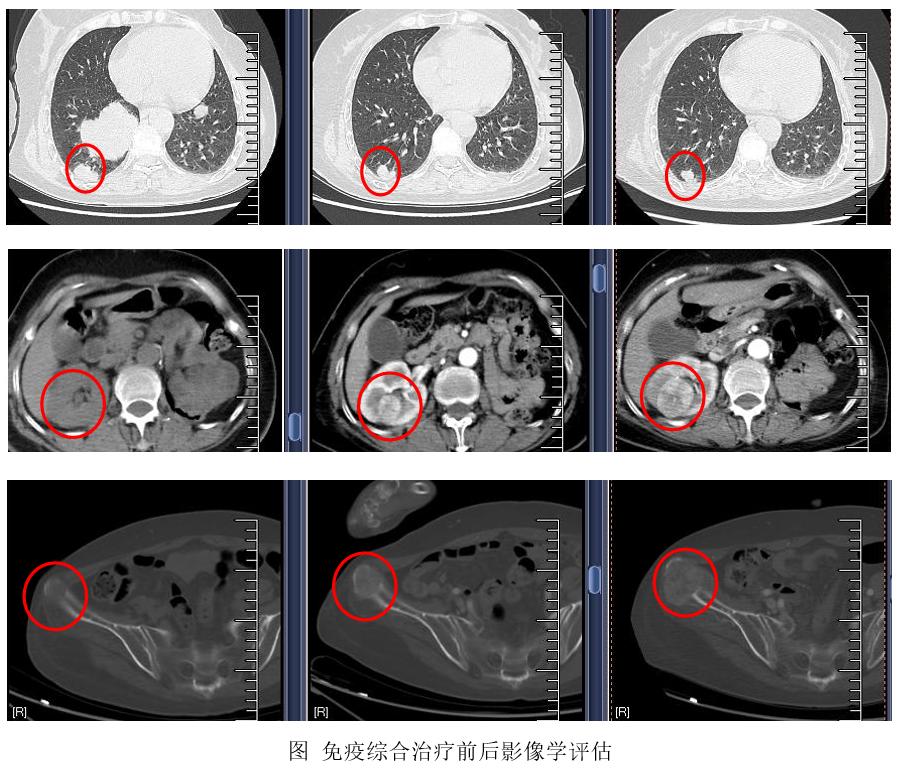

2020-02-05治疗中期,肺部多个病灶缩小明显,腹壁、右侧肾脏病灶、右侧髂骨病灶及额顶头皮包块较前稳定。

2020-04-21个体化新抗原肽纳米疫苗联合抗PD-1抗体的免疫综合治疗结束,肺部多个病灶仍持续缩小,腹壁包块、头皮包块稳定,右侧肾脏病灶及右侧髂骨病灶较前有所进展。

这是一例非常晚期肾透明细胞癌(far advanced RCC)病例,转移部位多,肿瘤负荷大。患者治疗依从性偏差,一直门诊口服用药及随访。经一线舒尼替尼,二线安罗替尼+复方环磷酰胺治疗,患者的肿瘤起初有一定程度地缩小,但因副作用问题、依从性问题,患者自行停药后病情持续进展。我们采用新抗原纳米疫苗+抗PD-1抗体的免疫综合模式,患者出现混合疗效,肺部多个病灶明显缓解,但是右侧髂骨和右肾病灶较前进展,后续计划针对患者右侧髂骨及头皮的包块姑息性放疗,抗血管生成药物治疗或新抗原反应应免疫细胞治疗也是治疗选项。总结来说,基于个体化新抗原肽纳米疫苗和抗PD-1抗体的综合免疫治疗模式,给如此晚期的肾透明细胞癌患者带来了一定程度的获益,进一步提示精准免疫治疗临床前景看好。